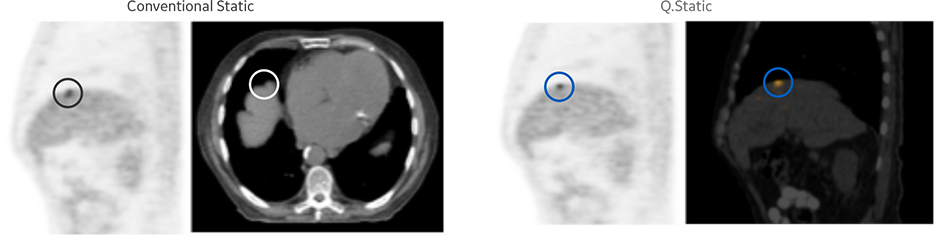

Increased PET sensitivity with TOF and QStatic